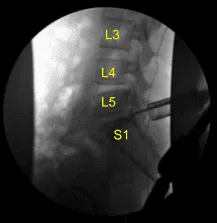

Se utilizó microdisección de Penfield para explorar el espacio epidural ventral y luego se empleó un retractor de raíz nerviosa para retraer la raíz nerviosa S1. Se utilizaron varios ganchos nerviosos para resecar la hernia discal que se extirpó con rongeurs microhipofisarios.

Se recogieron los fragmentos de disco herniado y se enviaron a patología para su análisis. Se identificó un defecto anular y se amplió con un bisturí #15 con bayoneta con cuchilla. La neurolisis se realizó con microinstrumentos de la raíz nerviosa S1, permitiendo una retracción suficiente para eliminar completamente los múltiples fragmentos herniados de disco hasta que, circunferencialmente, la raíz nerviosa S1 quedó completamente descomprimida, así como el saco tecal ventral. Esto se confirmó con ganchos nerviosos, microinstrumentos de Penfield y fluoroscopia.